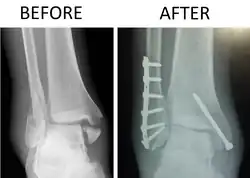

Fratura trimaleolar, antes e depois da cirurgia.

Fratura trimaleolar ou fractura de Cotton é um tipo de lesão do tornozelo caracterizada por fratura do maléolo lateral (na fíbula distal), do maléolo medial e da parte posterior da tíbia distal. Esse trauma é frequentemente acompanhado por lesão e luxação dos ligamentos tíbio-fibulares (sindesmoses).[1]

O reparo cirúrgico é uma redução ortopédica (reposicionamento dos ossos), osteossíntese com placa e parafusos e imobilização com gesso. Nos primeiros duas semanas sem andar e nas quatro semanas seguintes com bota de gesso, que permite pisar. Em idosos o prazo é o dobro (quatro semanas sem pisar, mais oito semanas com bota de gesso). O tratamento não cirúrgico pode ser considerado nos casos em que o paciente tem problemas de saúde significativos que desaconselham uma grande cirurgia.[3]